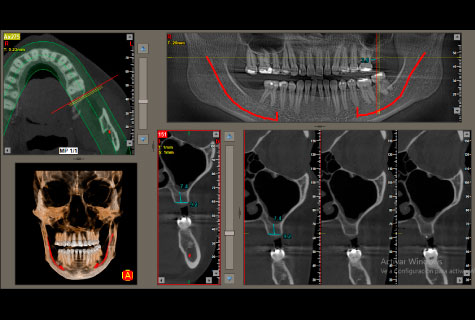

Contamos con un equipo tomográfico dental de los más modernos del país con tecnología de ultima generación para obtener magníficos resultados con una excelente calidad de imagen.

- Único que incluye programa para colocación de implantes virtual.

- Marcación del dentario inferior para un mejor diagnóstico.

Tomografía Cone Beam

- Tomografía de maxilares

- Tomografía de sector